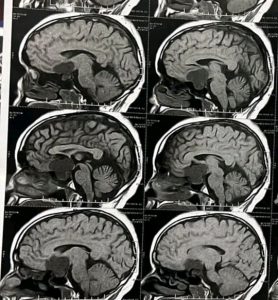

قصة نجاح جديدة سطرها فريق طبي بقسم جراحة المخ والأعصاب، بالتعاون مع قسمي الأنف والأذن والحنجرة والتخدير بمستشفي سوهاج الجامعي، عقب استئصال ورم بقاع الجمجمة ضاغط على العصب البصرى، أدى الى فقدان البصر بصورة كاملة، لشاب عمره ١٩ سنة يدعي ” أ.ع ” في العقد الثاني من العمر، صرح بذلك الدكتور حسان النعماني رئيس الجامعة.

وقال النعماني أن الفريق الطبي بمستشفي الطوارئ بمدينة سوهاج الجديدة، قام بإجراء التدخل الجراحي السريع والدقيق للتخفيف من الأعراض التي كان يعاني منها وتمثلت في الآلام وعدم الوعي والفقدان التام للبصر، وذلك بعد خضوعة لجراحة استغرقت أكثر من ٦ ساعات متصلة أسفرت عن استئصال “الورم” بنجاح وعودة الرؤية بوضوح.

ومن جانبه أوضح الدكتور مجدي القاضي عميد كلية الطب البشري ورئيس مجلس ادارة المستشفيات الجامعية، انه تجهيز المريض على وجه السرعة لاستثمار اخر فرصة لعودة البصر، فتم تشكيل فريق جراحى ذو مهارة عالية بقسم جراحة المخ والأعصاب، بالاشتراك مع قسم الانف والاذن والحنجرة، لعمل تدخل جراحى دقيق ميكروسكوبي بإستخدام المنظار الجراحى فى جراحة دقيقة امتدت أكثر من ٦ ساعات متصلة، تكللت بالنجاح.

وأوضح الدكتور مؤمن المأمون رئيس قسم جراحة المخ والأعصاب انه تم استقبال شاب عمره ١٩ سنة يعانى من فقدان تام بالبصر لمدة ٣٠ يوم مع صداع مزمن واضطراب بدرجة الوعى، وعلى الفور تم التعامل مع المريض وعمل الاشعات اللازمة، ليتم الكشف عن وجود ورم بقاع الجمجمة ضاغط على العصب البصرى، ادى الى فقدان البصر بصورة كاملة، موضحاً انه تم اجراء الجراحة للمريض بنجاح ومازال يتلقي العلاج بالمستشفي، بعد خروجه من العناية المركزة الى غرفة الملاحظة، للاطمئنان على درجة الوعى والوظائف الحيوية.